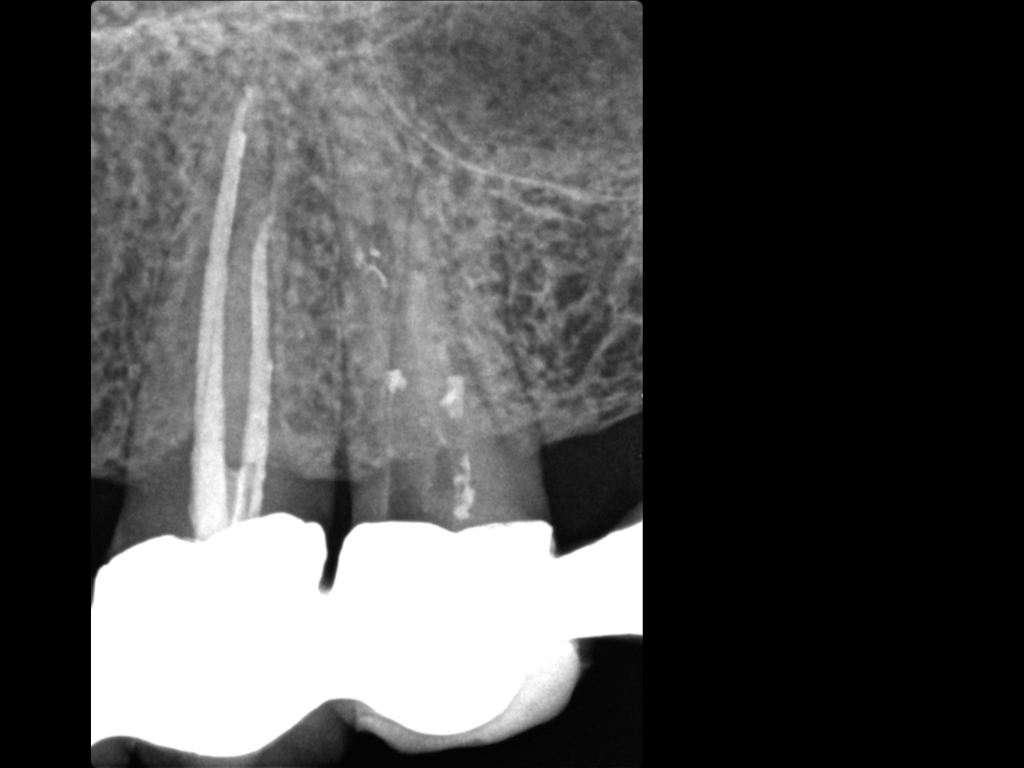

Es ist zu sehen … (2)